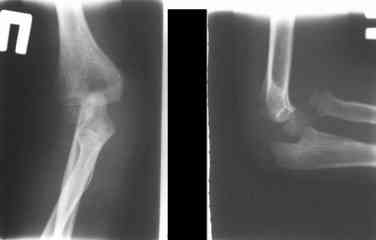

Данную методику применили впервые.  После артролиза очевидная

нестабильность головки луча. После остеотомии локтевой, вправления и

стабилизации аппарата головка луча при движениях на месте. Первые

впечатления- "Либо чудо,либо фокус" (с) :))

1 подвывих головки лучевой кости в положении супинации-

через 2 недели после операции- под ЭОП: аппарат разблокирован,

повторное вправление головки, стабилизация аппарата.